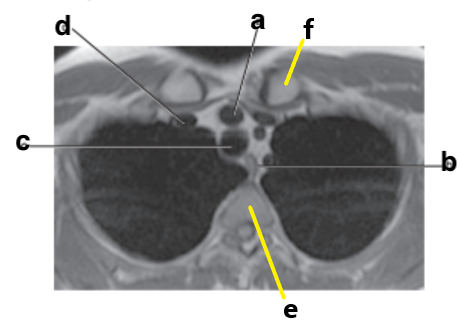

What is letter b ?

Esophagus

Which letter is the Descending aorta ?

f

What is letter e ?

Vertebral body